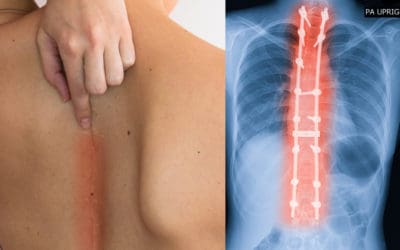

APA ITU SKOLIOSIS?

DAN BAGAIMANA PENGOBATANNYA?

Skoliosis adalah kelainan yang terjadi pada rangka tubuh yang berupa kelengkungan pada tulang belakang. Sebanyak 75-85% kasus skoliosis merupakan idiopatik, yaitu kelainan yang tidak diketahui apa penyebabnya.

Sedangkan 15-25% kasus skoliosis lainnya merupakan efek samping yang diakibatkan karena menderita kelainan tertentu, seperti distrofi otot, sindrom Marfan, sindrom Down, dan penyakit lainnya.

Berbagai kelainan tersebut menyebabkan otot atau saraf di sekitar tulang belakang tidak berfungsi sempurna dan menyebabkan bentuk tulang belakang penderita menjadi melengkung.

Mengapa setelah operasi skoliosis punggung tetap tampak menonjol sebelah?

Skoliosis merupakan kelainan tiga dimensi pada tulang belakang, dimana tulang belakang tidak hanya melengkung ke samping, tetapi juga mengalami rotasi (twist). Operasi skoliosis punggung akan dibahas lebih lanjut. Rotasi ini dapat terlihat jelas saat pemeriksaan...